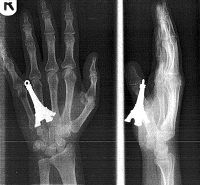

An image, obtained Friday in London, shows X-rays of a metal key ring Eiffel Tower embedded in Amy Preston’s hand.

She was jogging when she fell and landed on the key ring. The injury required stitches, but Ms. Preston is expected to recover. (Agence France-Presse/Getty Images)